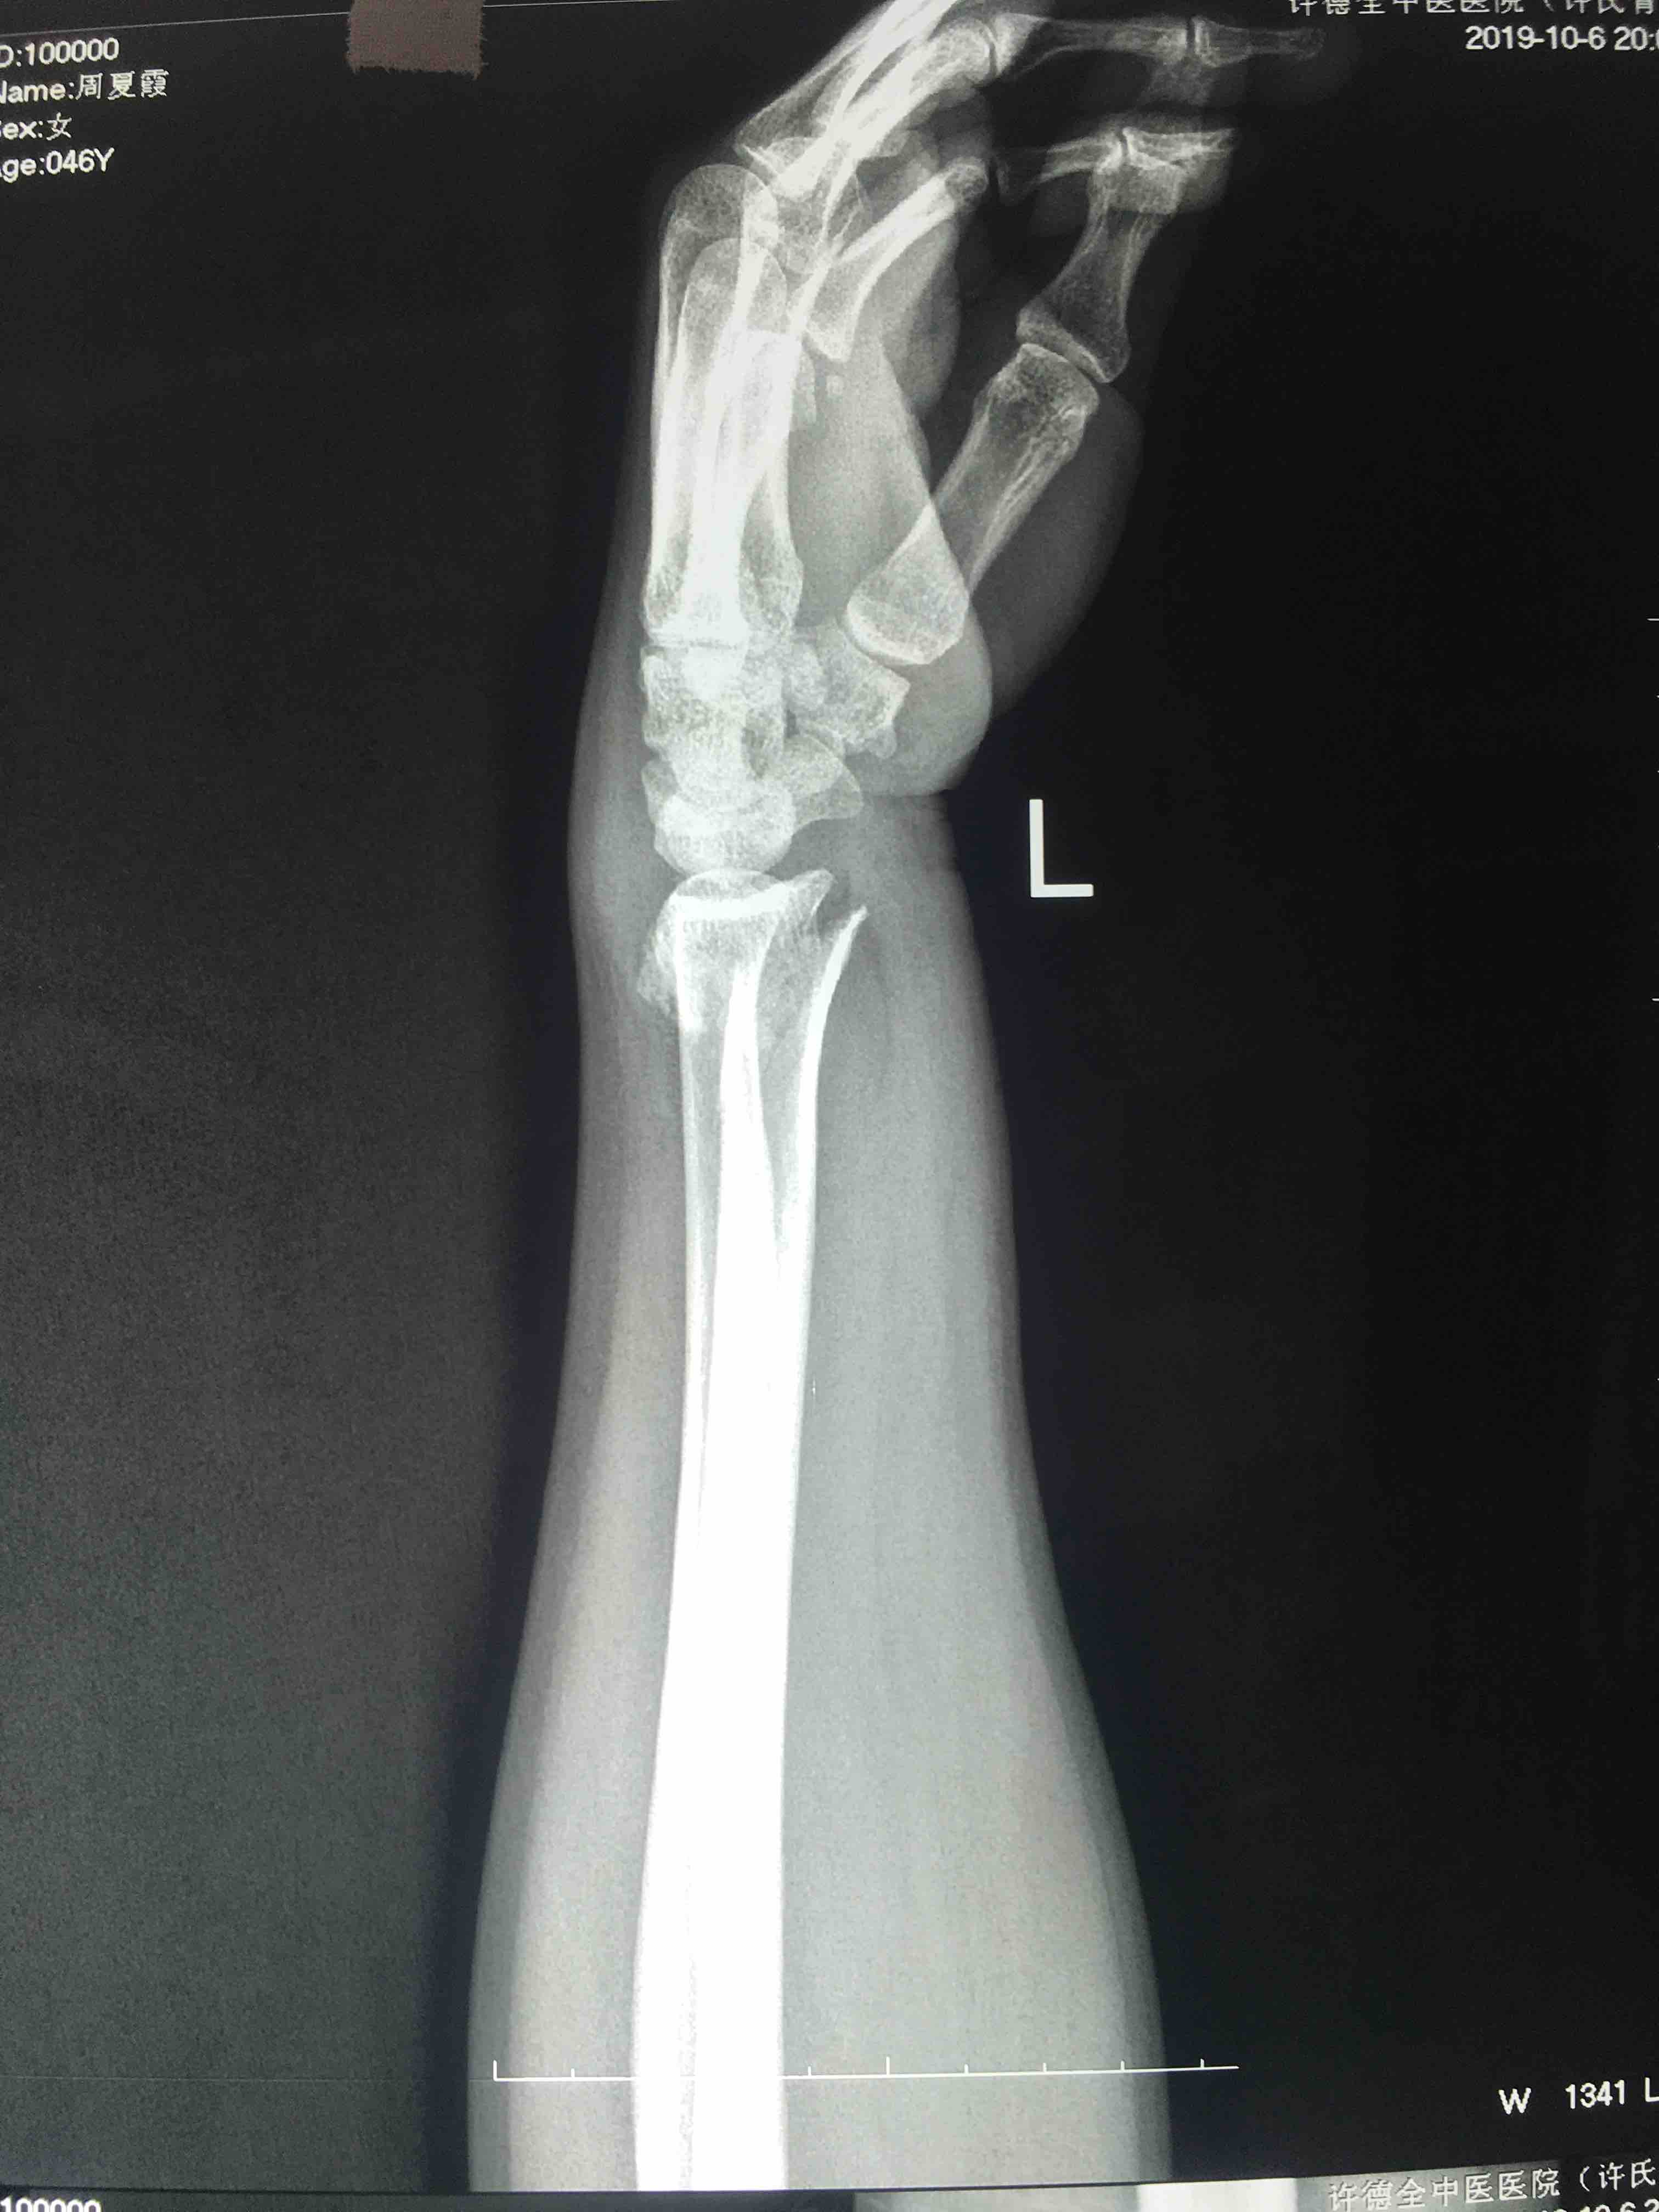

桡骨远端粉碎性骨折(锁定固定)

摔伤后左腕部肿痛,畸形,活动受限1小时入院。既往身体健康,无特殊不良嗜好。

生命体征平稳,心肺复未见异常。左腕部肿胀,畸形,局部皮色皮温正常,压痛及纵叩痛阳性,末梢血运感觉正常。

在臂丛麻醉下行切复内固定术,术后抗炎消肿等处理,